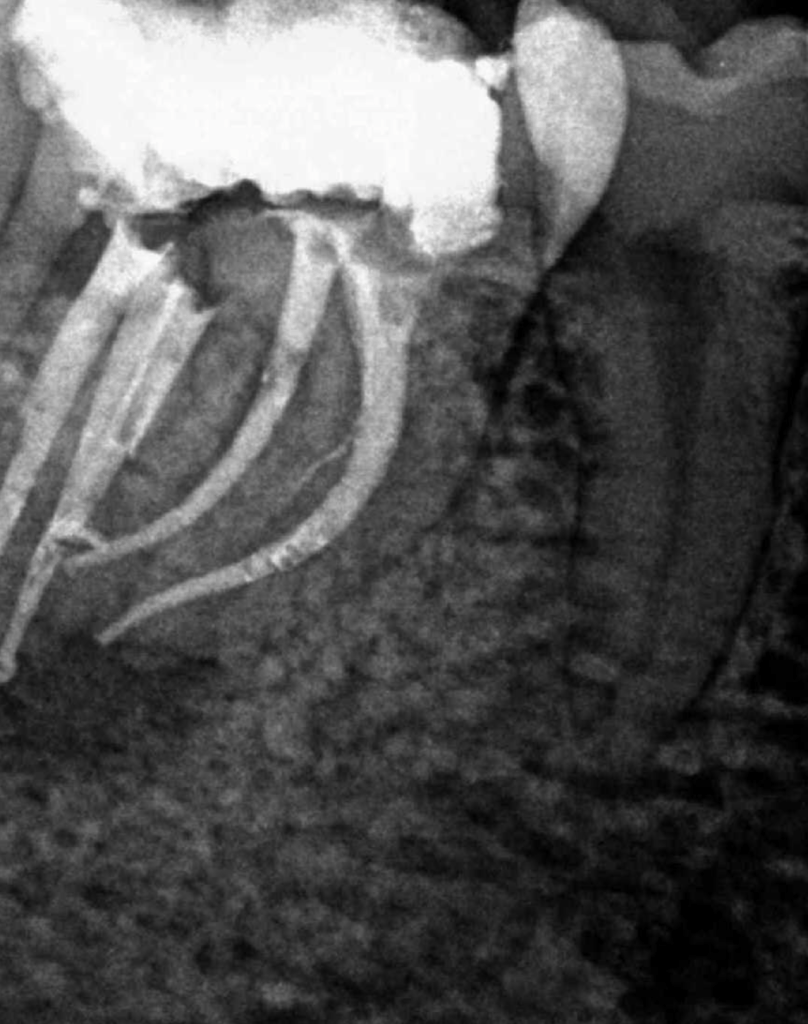

Molar gran curvatura bifurcación palatino